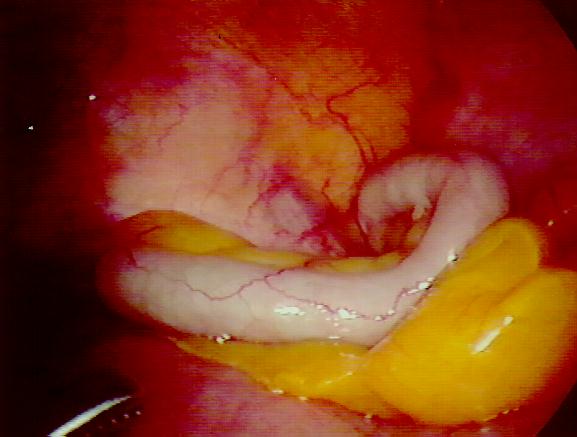

• In human anatomy, the appendix (or vermiform appendix; also cecal (or caecal) appendix; also vermix) is a blind-ended tube connected to the cecum (or .

• The appendix is a fingerlike pouch attached to the large intestine and located in the lower right area of the abdomen. Scientists are not sure what the .

• Jun 1, 2011 . The appendix is a closed-ended, narrow tube up to several inches in length that attaches to the cecum (the first part of the colon) like a .

• In humans, the vermiform appendix is a small, finger-sized structure, found at the end of our small caecum and located near the beginning of the large .